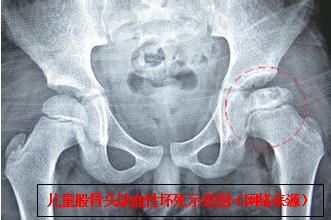

骨伤六科副主任中医师陈凯奇当时正在休假,接到该患儿外伤病例电话邀诊后,立即组织该团队主治医师陈宏慈和医护人员启动假日接诊预案,进入相关接诊诊疗工作程序。患儿16时45分送达骨伤六科诊室,当时烦躁、哭闹不止。医疗团队快速、专业地开展诊治流程,经检查发现,幼儿左下肢短缩、屈曲、内收、内旋畸形,弹性固定,活动受限,于患侧髋臀肌部可触及隆起。再详细查阅外院X光片,结合幼儿遭遇外力撞击的情况,确诊为:左髋关节脱位(后脱位)。

经过2分钟的中医正骨手法治疗后,下午17时35分,患儿复查X光检查结果出来了,骨伤六科医疗团队看到幼儿左髋关节脱位复位后关节位置结构正常,如释重负地松了一口气。

该团队相关负责人介绍,该患儿如不及时快速准确将脱位的髋关节整复,会引发并发症,进而导致股骨头缺血性坏死、髋关节生长紊乱、神经损伤、复发性脱位、创伤后骨关节炎、骨化性肌炎、股骨头创伤性分离。而其中最危急,要与时间赛跑的就是股骨头缺血性坏死,所以,必须在伤后24 小时内完成脱位髋关节的复位。